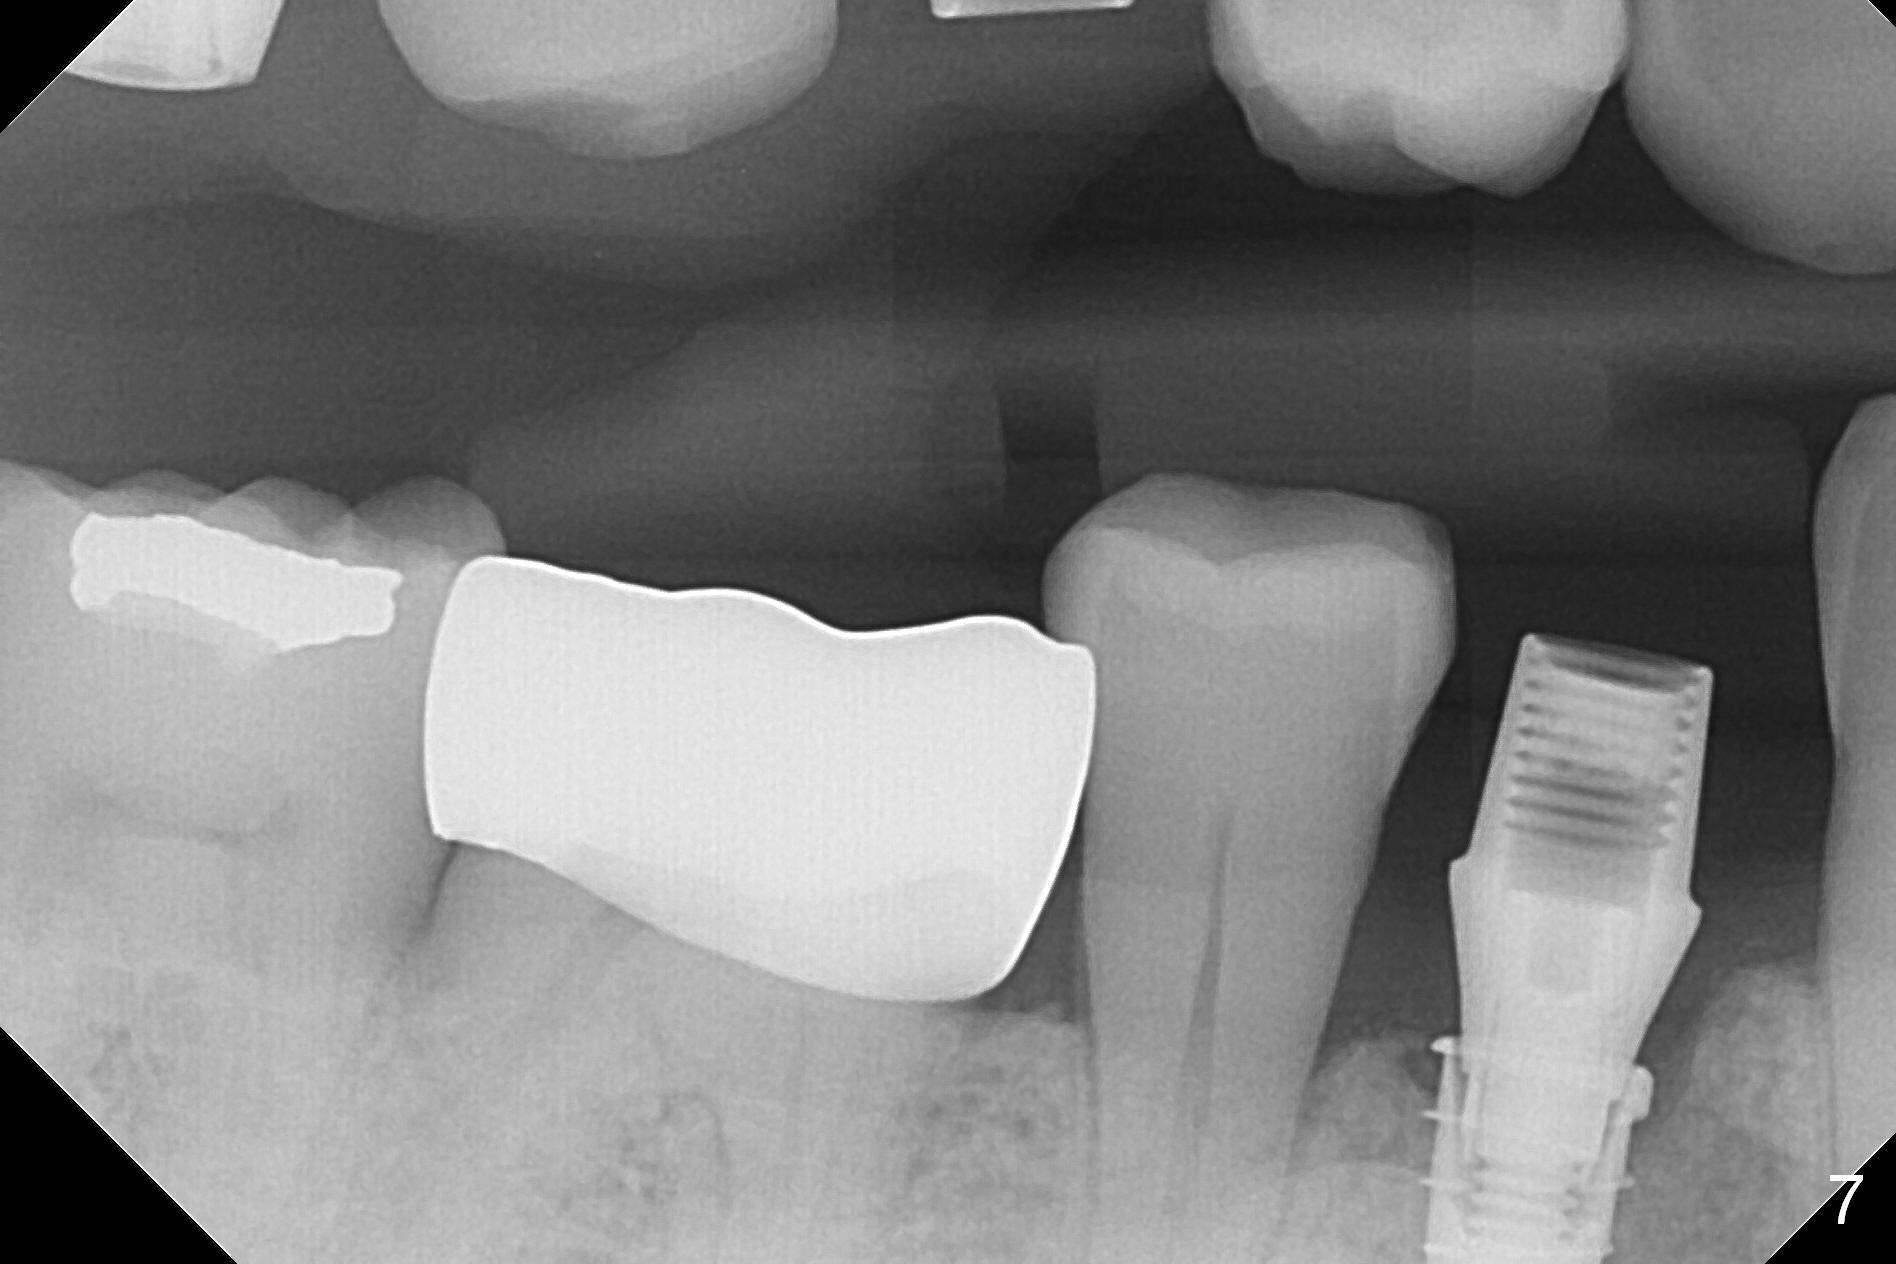

In fact the mesiodistal space of the site of #28 is within normal limit. The buccal plate atrophy is striking (Fig.1) with a fistula (^, associated with underlying residual root tip). When the flaps are raised, the ridge is triangular with the lingual plate (Fig.2 *) higher than the buccal one. Because of the slope, the multiple-drill approach is adopted in stead of single-drill one, because the marking bur is wobbling after 1.6 mm osteotomy at 13 mm (Fig.3). After placement of a 4x11 mm implant, a 4.5x4(2) mm abutment is inserted (Fig.4). The abutment and the implant act as a mesh (framework) so that bone graft and collagen membrane can be laid upon them buccolingually. When the flaps are sutured, there is less tension than that without the abutment. Furthermore, the buccal tissue volume seems to be increased (Fig.5 (<: fistula, which should heal soon), as compared to Fig.1). Tale photos to show effectiveness of the simultaneous GBR and disappearance of the fistula. Three months postop (Fig.6,7 (incomplete abutment seating)), the implant is loaded for intrusion of the opposing supraerupted tooth. The patient returns with chief complaint of food impaction between #27 and 28 three years 7 months post cementation; there is an open contact. Before pick up impression the distal convex surface of #27 is trimmed. The repaired crown has tight proximal contacts before (Fig.9,10) and after (Fig.11) retightening and cementation.